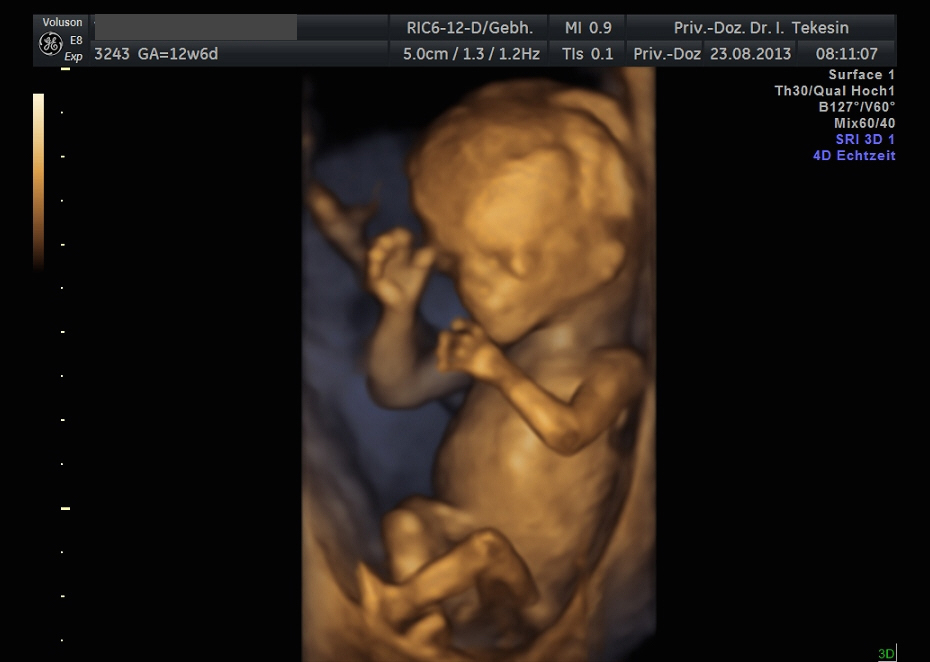

3D-/4D-Ultraschall (optional)

Immer mehr werdende Eltern interessieren sich für die faszinierenden Bilder, die dieses Verfahren liefert. Die plastische, dreidimensionale Darstellung der Oberfläche des Gesichts und anderer Körperregionen wird durch spezielle Bildrekonstruktion in schnellen Rechnern erreicht. Auch einzelne innere Organe oder „Gefäßbäume“ können von allen Seiten betrachtet werden. Viele dünne Schnittebenen (2D) werden zu einer gemeinsamen 3D-Sichtweise im Computer des Ultraschallgerätes zusammengeführt. Unter einem 4D-Ultraschall versteht man darüber hinaus eine 3D-Ultraschalluntersuchung unter Echtzeitbedingungen. Anstatt nur statische Bilder anzuzeigen, erfasst ein 4D-Ultraschall die Bewegungen des Kindes, weshalb er auch als „Live-3D-Ultraschall“ bezeichnet wird.

Diese Vorgehensweise ermöglicht äußerst realistische Bilder, bei denen sogar Gestik und Mimik des Kindes in bewegten Sequenzen festgehalten werden können. Die Untersuchung kann wie auch der normale Ultraschall während des gesamten Schwangerschaftszeitraums durchgeführt werden. Möchte man das Ungeborene komplett sehen, wird die 12. bis 16. Schwangerschaftswoche empfohlen, die Zeit zwischen der 28. und 33. Schwangerschaftswoche eignet sich besonders zur präzisen Darstellung einzelner Körperteile

Wir sehen in diesem modernen Verfahren in erster Linie eine ergänzende Maßnahme bei speziellen Fragestellungen bezüglich Herz, Gehirn oder Skelett und vor allem bei Verdacht auf eine fetale Besonderheit.

Kind in der 12. Woche

Kind in der 12. Woche (3D-Darstellung)